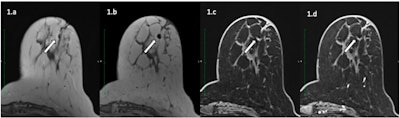

A 57-year-old patient with an invasive ductal carcinoma marked by an O-Twist metallic marker and treated with neoadjuvant chemotherapy underwent a presurgical MRI on a Siemens 3T with T2-weighted (a), T1-weighted (b), and 3D T1-weighted Dixon before (c) and after (d) contrast injection. Metallic marker is responsible for a hyposignal artifact with hyperintense peripheral halo. However, diagnostic confidence was 3 for both readers. Despite the relatively small size of the artifact, the small initial size of the tumor (7 mm) resulted in uncertainty in appreciations of both readers in the presence of the metallic marker artifact. The patient was considered rCR but histology revealed the presence of residual tumor. All figures courtesy of Dr. Matthias Hugot et al and European Journal of Radiology.

A 57-year-old patient with an invasive ductal carcinoma marked by an O-Twist metallic marker and treated with neoadjuvant chemotherapy underwent a presurgical MRI on a Siemens 3T with T2-weighted (a), T1-weighted (b), and 3D T1-weighted Dixon before (c) and after (d) contrast injection. Metallic marker is responsible for a hyposignal artifact with hyperintense peripheral halo. However, diagnostic confidence was 3 for both readers. Despite the relatively small size of the artifact, the small initial size of the tumor (7 mm) resulted in uncertainty in appreciations of both readers in the presence of the metallic marker artifact. The patient was considered rCR but histology revealed the presence of residual tumor. All figures courtesy of Dr. Matthias Hugot et al and European Journal of Radiology.Hugot and his colleagues from Geneva University Hospital have just published the findings of a study on this topic. The results, published on 28 July in the European Journal of Radiology, show that the diagnostic performance of preoperative MRI after neoadjuvant chemotherapy (NAC) for the prediction of Pathological Complete Response (pCR) did not differ statistically in the presence or absence of metallic markers.